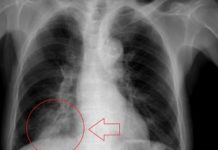

On the PA view, the cardiac borders are smaller and more defined. Given the way the x-ray beam works, the heart appears smaller and with sharper borders on the PA view. The reason is that the patient’s chest (anterior) is against the x-ray film with the beam entering from posterior (P) to anterior (A) – hence the term “PA.” Similarly, the AP view is when the beam enters from front to back with the x-ray film at the back of the patient – therefore, the heart is magnified and the margins are minimally less sharp.